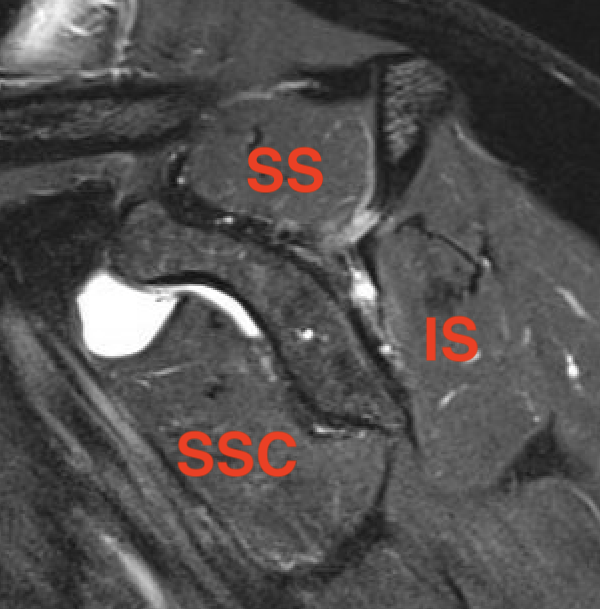

MRI

Measure tear in the coronal and sagittal plane

Massive rotator cuff tear of the supraspinatus and infraspinatus tendon - retracted to glenoid